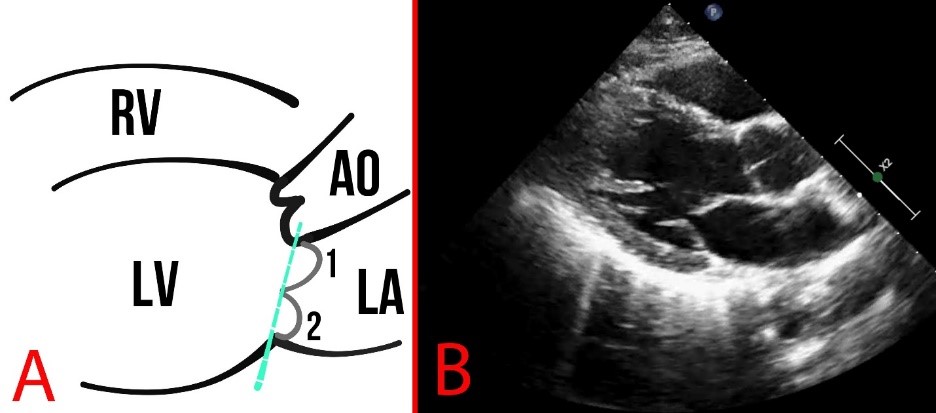

MVP is defined as the billowing or bulging of MV leaflets more than 2 mm above the mitral annulus in a long-axis view (Fig. 4).

Fig. 4. MVP. (A) Schematic presentation of MVP. The arrows show the MV, 1 and 2 represent the MV leaflets, the line (3) shows the mitral annulus, and the arrow depicts the coaptation zone. (B) Echocardiography of a patient with MVP, the red arrow indicates MVP.